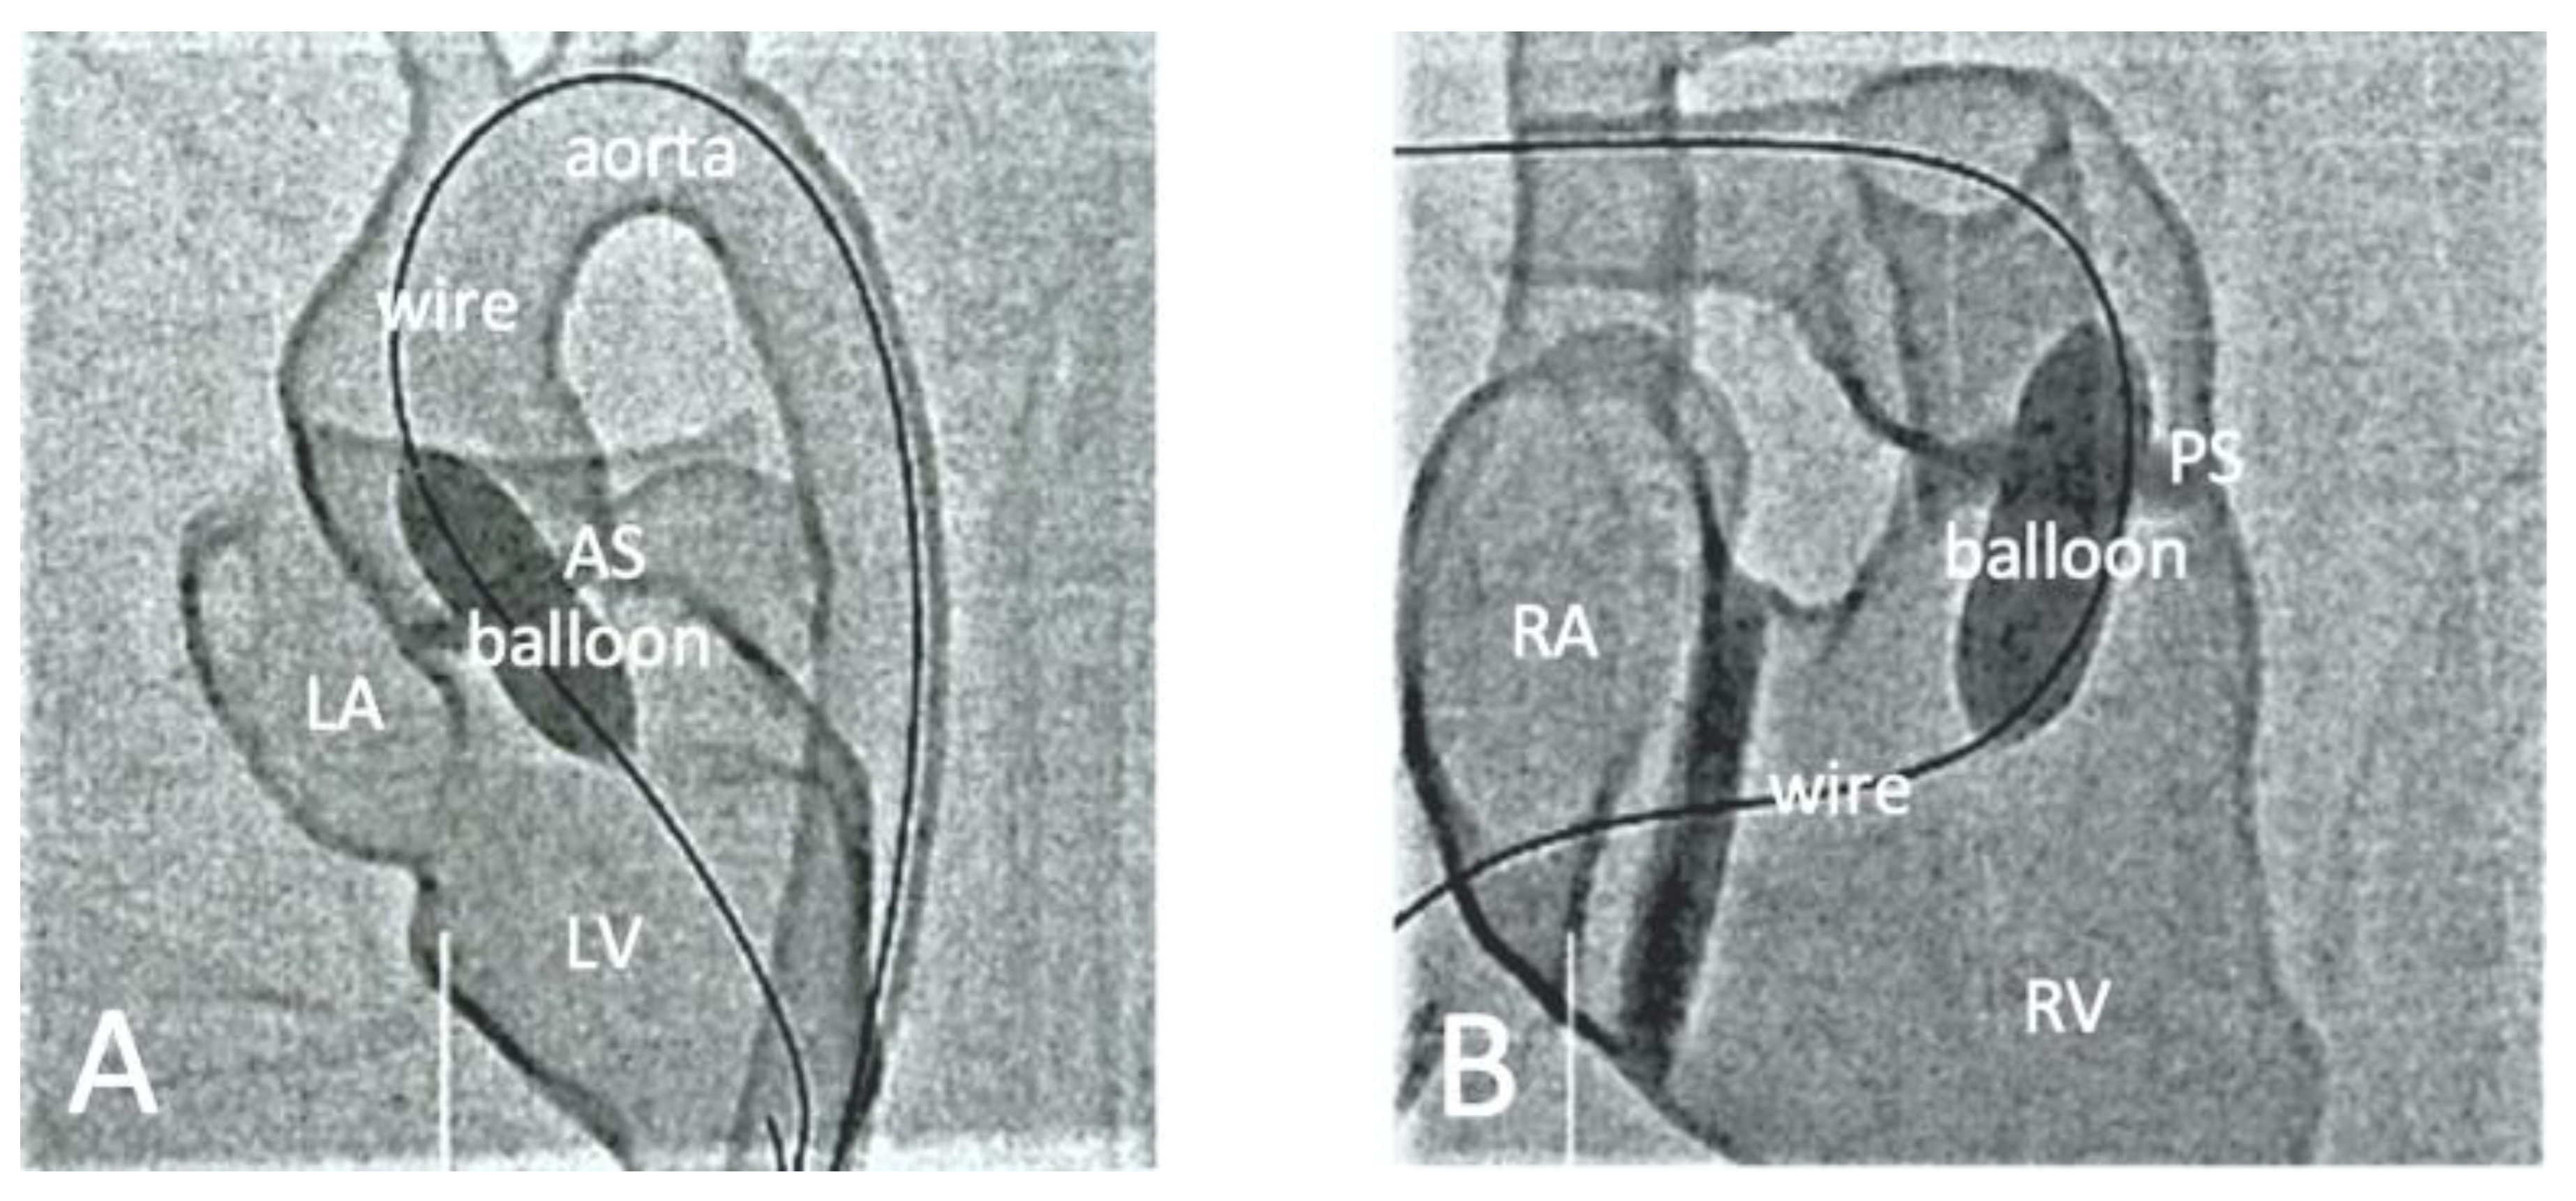

| Brunner et al. [87] | Cross-sectional study | Nineteen medical students and doctors participated in the hands-on training program. | CT | Hands-on training on simulation of interventional cardiology procedures on common CHD models. | Mimics (Materalise, Belgium) | Agilista 3200W Polyjet 3D printer | Silicone rubber | Practicing on 3D-printed models significantly reduced the mean fluoroscopy time and increased confidence in interventions on real patients. |